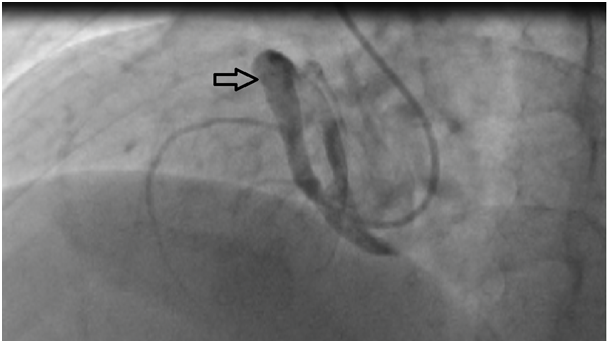

27years old male patient admitted to our outpatient clinic with progressive, pleuritic chestpain unrelated to exertion for a month with no significant medical history. The patient was diagnosed with acute pericarditis at an center and receiving ibuprofen and colchium treatment for three weeks. There was no pathological finding on cardiacaus cultation, blood pressure was 110/80mmHg, heart rate was 110bpm. Electrocardiography showed sinustachicardia and minimal ST segment elevation in all leads. There was a slight cardiomegaly in chest X-ray (Figure 1). Cardiac markers and inflammatory marker were elevated; troponin-I 1112ng/L (0-100), CK748 U/L (0-190), CK-MB 95 U/L(3-25), ESR 65, CRP 75 was detected. Transthorasic echocardiography revealed a 45x60 mm of cavitary mass compressing the right atrial free wall along with pericardial effusion (Figure 2); which was the only location of pericardial effusion in his previous examination a month ago. The patient was admitted to CCU. An aneursym 100x70x60mm in diameter, originating from right coronary artery extending to right atriallateral wall border and compressing externally, which contains thrombus material in its cavity was detected in cardiac computed tomography (CT) (Figure 3). Coronary angiography revealed a giant aneurysm communicated with RCA (Figure 4) without any abnormalty on left coronary arteries. The patient was given to emergency surgery because of the risk of pericardial tamponade. Aneurysmectomy was done and the remained cavity was closed primarily. Pathological examination was reported as polymorpho nuclear leukocyte and mononuclear inflammatory cell infiltration without elastic fibers and a pseudoaneursym of the coronary artery. The patient was discharged without any complication.

Figure 4 Giant right coronary artery aneurysm in coronary angiography (Black arrow).